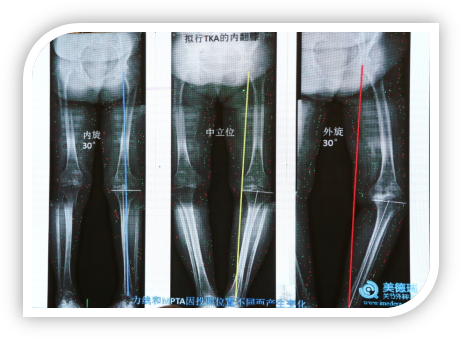

下图患者因半月板损伤就诊,在中立位时力线通过膝关节中心,在膝关节内旋30°时力线外移,当膝关节外旋30°时力线内移,测出的MPDA是不同的,外旋下测出的MPDA是小的,完全可能因为照相的问题测出来的MPTA符合HTO的要求,但实际并非如此。